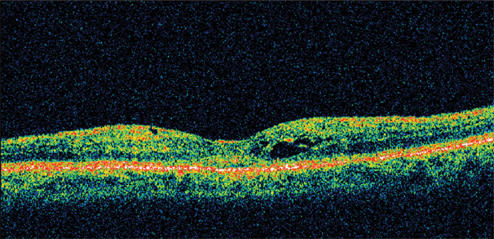

A 71-year-old man who had cataract surgery 3 months earlier was a known steroid responder with elevated IOP following surgery. At presentation, his visual acuity was 20/63. He had a fine epiretinal membrane and CME OD. Retinal thickness was 501 μm on OCT (Figure 4).

Figure 4. A 71-year-old man, who had cataract surgery 3 months earlier, presented with visual acuity of 20/63. He had a fine epiretinal membrane and CME OD. Retinal thickness was 501 μm on OCT.

Figure 5. One month following treatment with nepafenac, vision improved to 20/32 with a marked reduction in retinal thickness. By 12 weeks, visual acuity was still 20/32 with a retinal thickness of 261 μm and an improvement in the appearance of the fovea.

He was treated with nepafenac qid for 6 weeks and tapered over the ensuing 6 weeks. His vision improved to 20/32 by 1 month, with a marked reduction in retinal thickness. By 12 weeks, his visual acuity was still 20/32 with retinal thickness of 261 μm and an improvement in the appearance of the fovea (Figure 5).